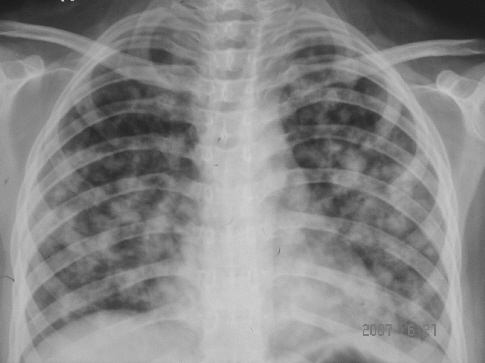

消炎治疗后复查

2007年5月9日病情未好转